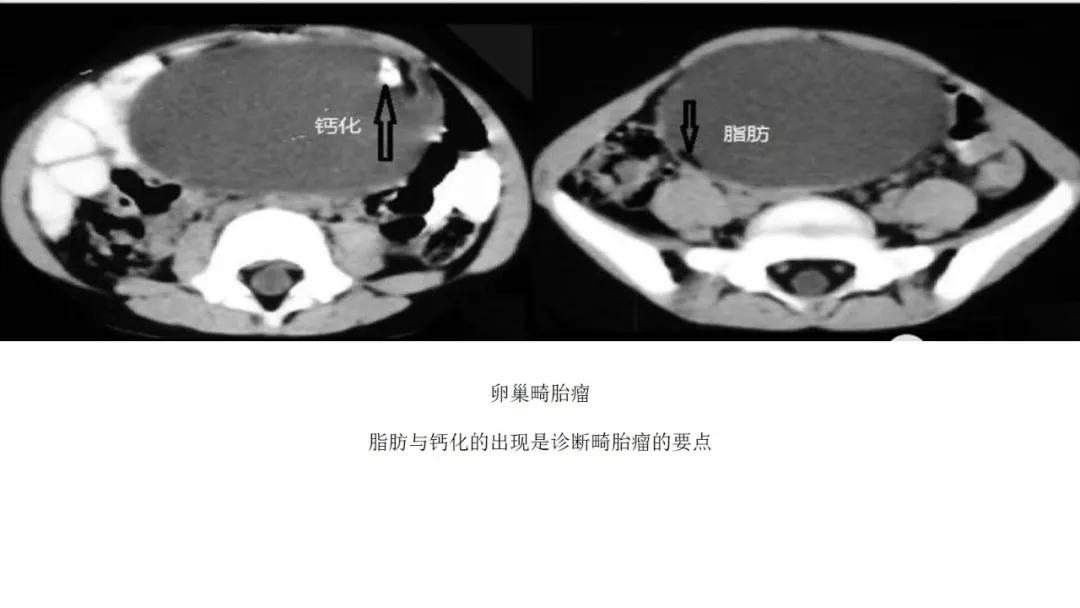

生殖细胞肿瘤占卵巢肿瘤的20%,以成熟畸胎瘤-皮样囊肿多见,良性多,恶性少。表现为囊实性混合性或实性肿块,大多数含有脂肪、钙化等特征。

良性者常呈囊性肿块,脂囊,脂液囊,液囊。少数混合成分,实性。壁光整可稍厚,囊内有脂、液分层现象,多数伴有粗大钙化或骨骼。

出现脂肪:畸胎瘤,囊性为主是成熟、实性为主是不成熟